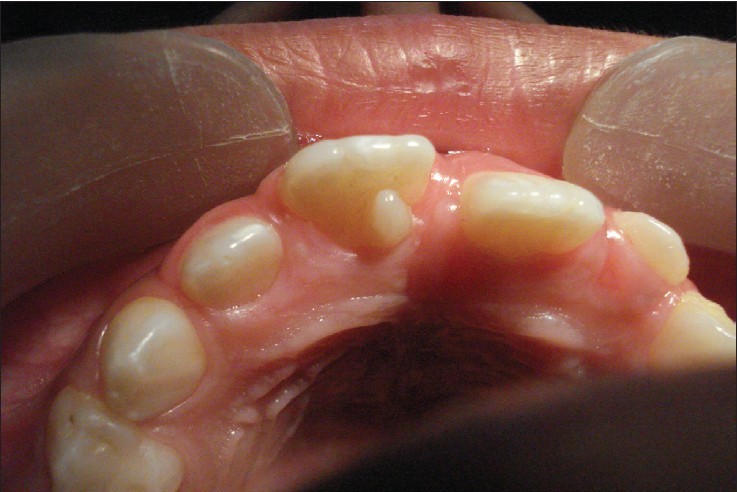

What is this kind of hyperdontia called?

Mesiodens